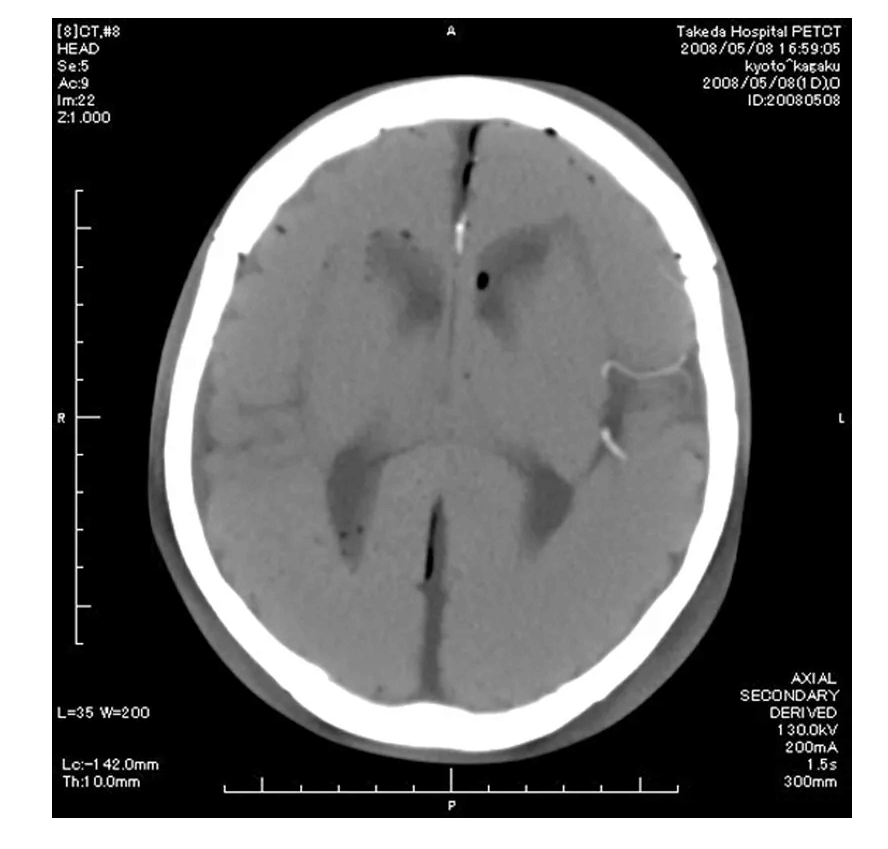

Das Angiographie Kopfmodell ist ein hochpräzises Trainingsmodell, das einen synthetischen Schädel in einen Kunststoffkopf integriert. In der linken Schädelhälfte sind die vordere und mittlere Hirnarterie nachgebildet und mit Kontrastmittel gefüllt, um realistische Trainingsbedingungen für die Angiographie zu schaffen. Die simulierten Arterien haben einen Durchmesser von 0,5 mm bis 4 mm und ermöglichen so eine detaillierte Untersuchung und Diagnose von Gefäßstrukturen im Gehirn. Dieses Modell ist besonders geeignet für medizinische Fachkräfte, die ihre Fähigkeiten in der Angiographie und Bildgebung von Gehirngefäßen verbessern möchten.

Mit Kontrastmittel gefüllte Arterien ermöglichen realistische Angiographie-Simulationen

Das Modell ist für den Einsatz in der Angiographie und der Gefäßdiagnostik ausgelegt, insbesondere für das Training der Bildgebungstechniken in der neurologischen Radiologie.